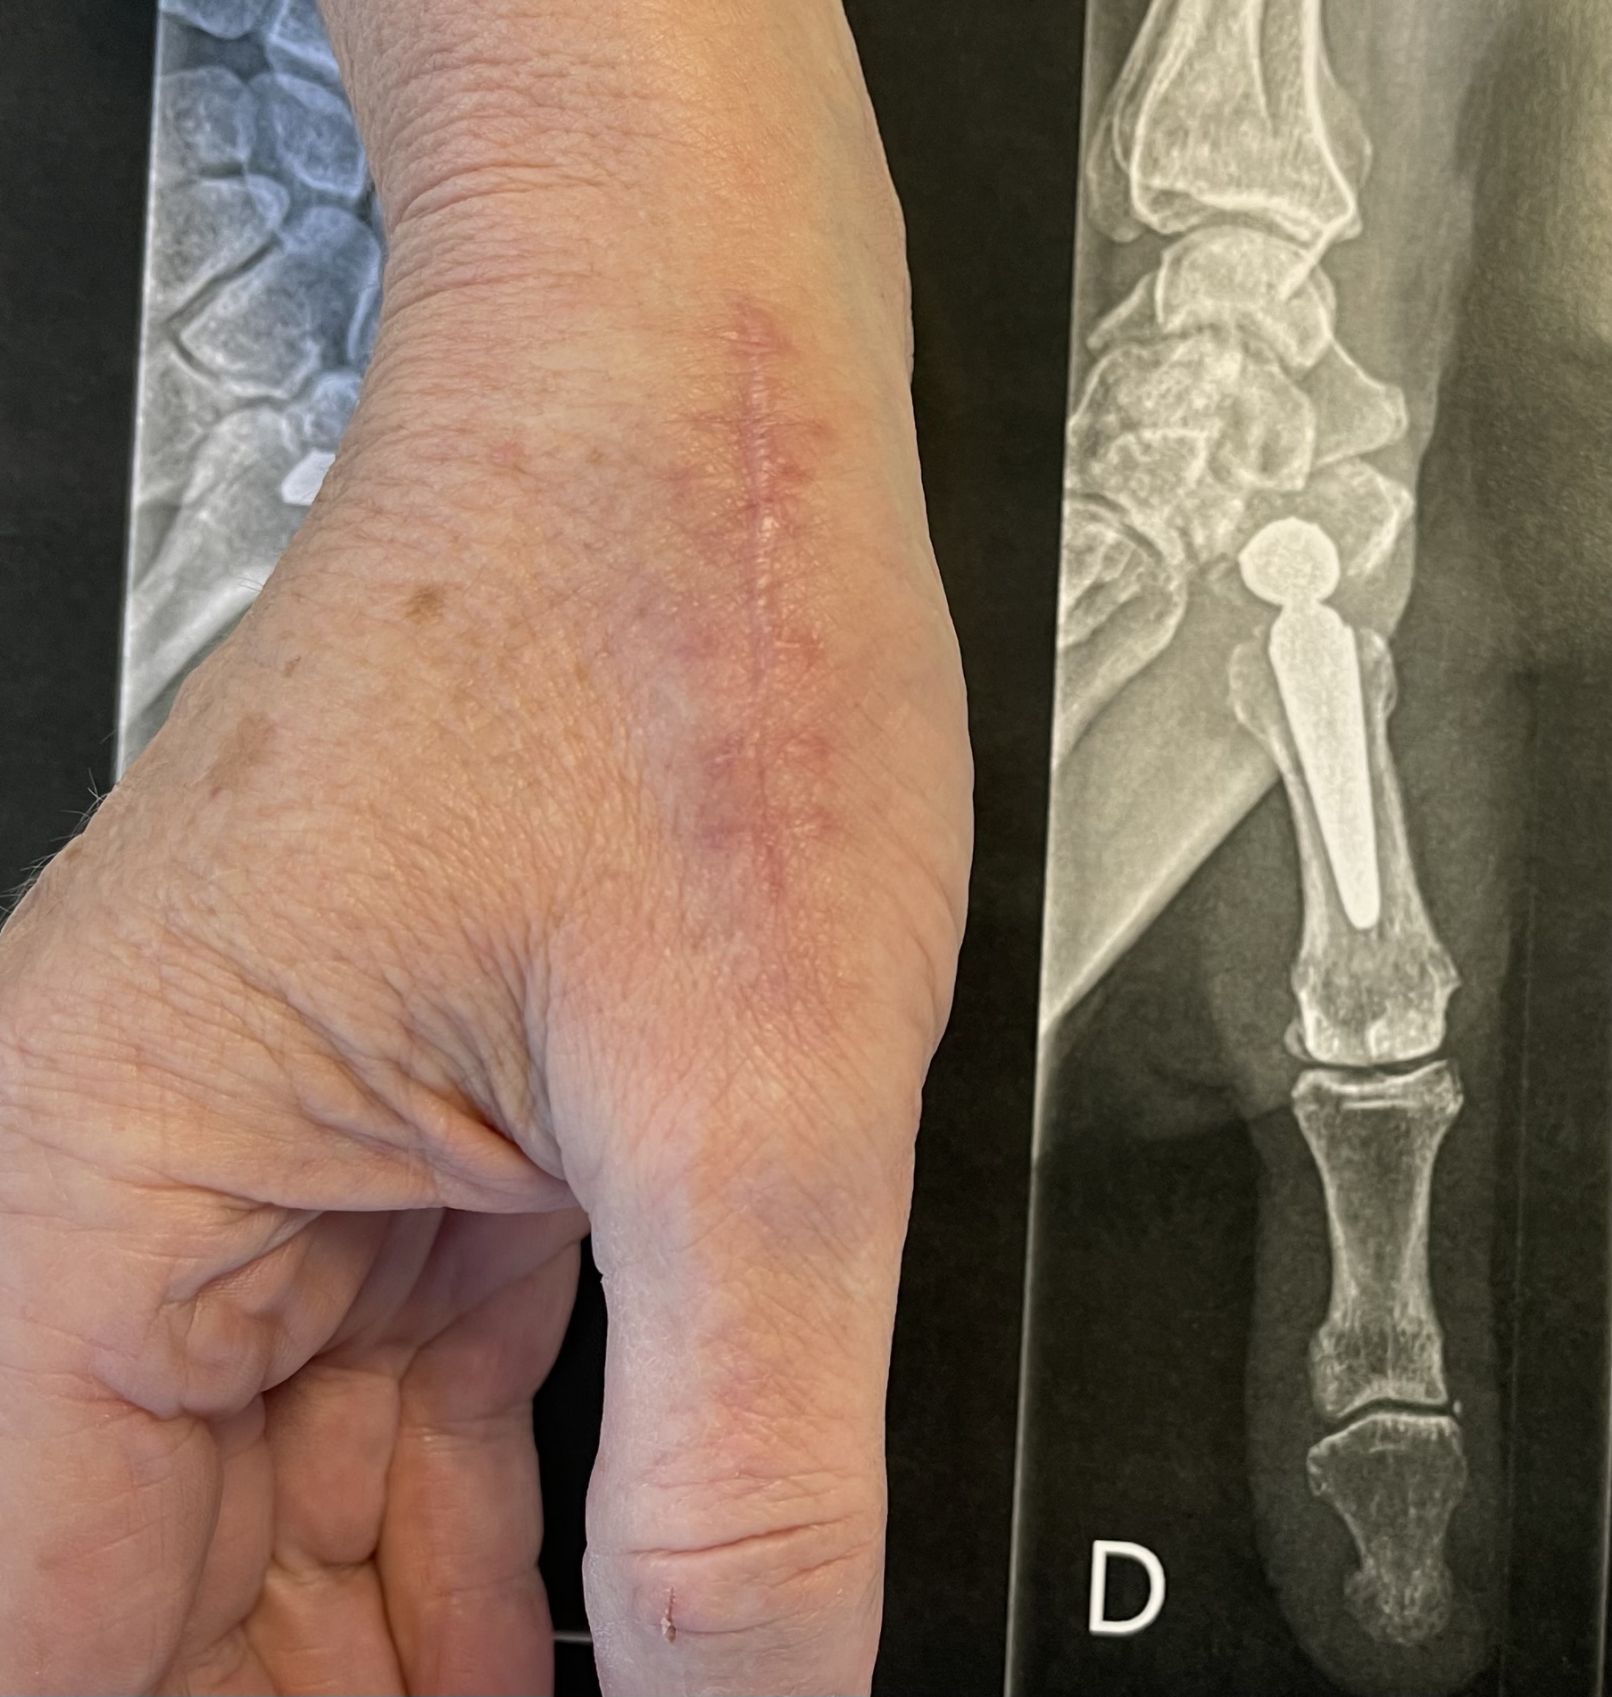

Prothèse trapézo-métacarpienne — cicatrice et radiographie post-opératoire

Cicatrice dorsale et radiographie post-opératoire